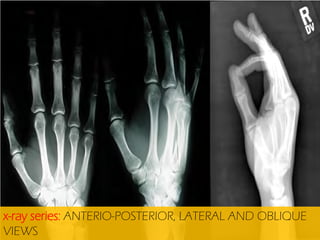

x-ray series: ANTERIO-POSTERIOR, LATERAL AND OBLIQUE

VIEWS